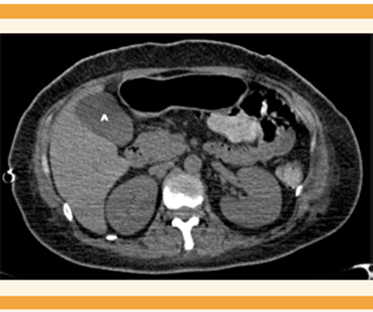

Al noveno día de hospitalización tuvo recaída en el estado clínico y requirió el uso de parámetros ventilatorios altos y FiO2 al 80%. En los estudios paraclínicos se advirtió incremento de los triglicéridos hasta 1087 mg/dL y elevación de las transaminasas al doble de los valores basales (fosfatasa alcalina 317 UI/L, gammaglutamil transferasa 669 UI/L, LDH 456 UI/L, alanino aminotransferasa 114 UI/L, aspartato aminotransferasa 105 UI/L), sin cumplir criterios de enfermedad hipertensiva del embarazo. La biometría hemática reportó leucocitosis de 25.6 x103 a expensas de segmentados y bandas, procalcitonina en 15 ng/mL y la TAC abdominal reportó colecistitis aguda, lodo biliar, imagen de doble riel en la pared de 8.5 cm, líquido perihepático y líquido libre en la cavidad abdominal. Figura 3

Figura 3 TAC contrastada abdominal. La vesícula biliar se observa con dimensiones de 92 x 41 x 40 mm, volumen de 78 cc, de contenido heterogéneo a expensas de imagen que condiciona líquido en su interior (A), la pared engrosada (8.5 mm) con escaso realce en fases contrastadas.